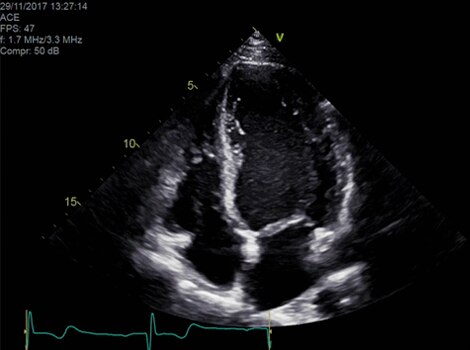

VividTM Family Cardiac Ultrasound Automated Function Imaging (AFI)

Assess left ventricular function and cardiac performance with clarity, improving clinical confidence. Read More

Vivid Family Cardiac Ultrasound

Vivid E95 with cSound performance makes 4D as easy as 2D to quantify left ventricular wall motion. Read More

Vivid™ Family Cardiac Ultrasound Automated Function Imaging (AFI)

Assess left ventricular function and cardiac performance with clarity, improving clinical confidence.